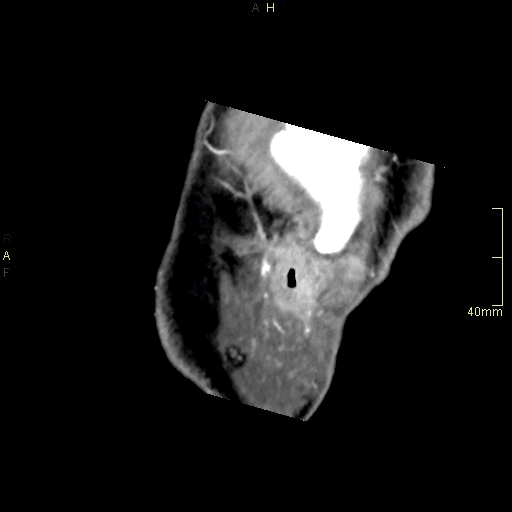

CT Sinuses Contrast- Soft Tissue window (axial)

CT Sinuses Contrast- Bone window (axial)